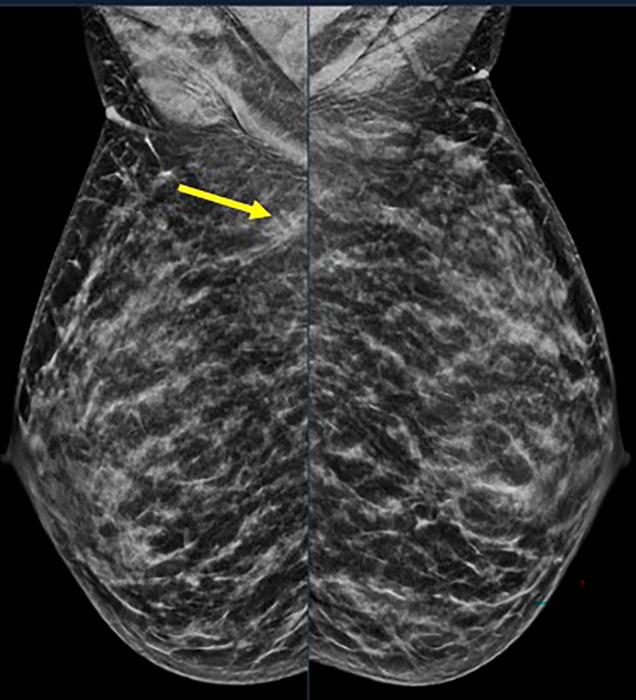

40-year-old patient presents for routine screening. Family history of paternal grandmother age 55. Extremely dense breast tissue is noted on mammography right and left mediolateral oblique (side angle) view. In addition, an area of architectural distortion is seen at the posterior right breast on right view (see arrow).